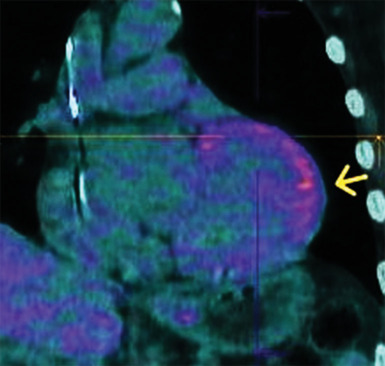

Sarcoidosis is a chronic inflammatory condition of uncertain origins, affecting multiple organs and characterized by the formation of granulomas. Cardiac involvement, known as cardiac sarcoidosis (CS), occurs in 5%-10% of cases and can lead to heart failure, arrhythmias, and sudden death. Distinguishing CS from other heart conditions poses a significant challenge. However, improved diagnostic techniques such as cardiac magnetic resonance (CMR) and positron emission tomography combined with computed tomography (CT) have enhanced recognition rates, replacing invasive procedures like endomyocardial biopsy. Clinical guidelines have further facilitated diagnosis. This case report underscores the diagnostic complexity of CS and highlights the emerging role of contrast-enhanced cardiac CT as a viable alternative to CMR, particularly in patients with contraindications to CMR.